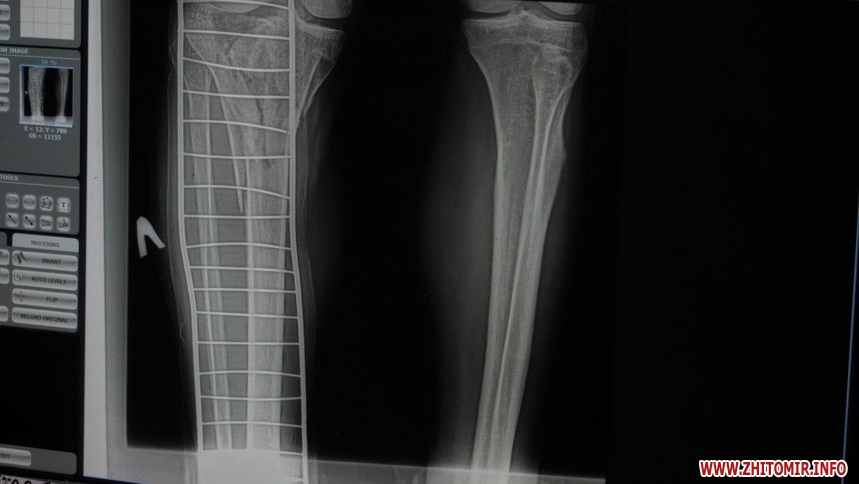

«Зараз розпочинається сезон, люди частіше використовують цю техніку і, відповідно, отримують травми. Цього року звернень ще не було, у минулому році зафіксували близько 30 звернень. Найпоширеніші – переломи верхніх кінцівок, переломи променевої кістки у типовому місці та кісточок гомілки. Було кілька випадків, коли травми потребували оперативного втручання та металоостеосинтезу», – розповідає в.о. завідувача ортопедо-травматологічного відділення КП «Лікарня №1» Житомирської міської ради Олександр Зубенко.